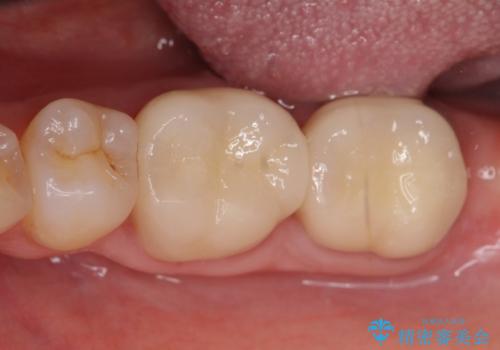

歯周外科手術終了後、歯茎の回復を待ち左下6、7ともにオールセラミッククラウン(スタンダード)による補綴を行いました。

今回用いたオールセラミッククラウンはジルコニアフレームという白い素材の上にセラミックを盛っているため、審美性が非常に高いのが特徴です。

また、ジルコニアは人工ダイヤモンドの材料にも使われているほど高い強度を持っており、そのためオールセラミッククラウンは審美性だけでなく、奥歯やブリッジの補綴も可能とするクラウンです。